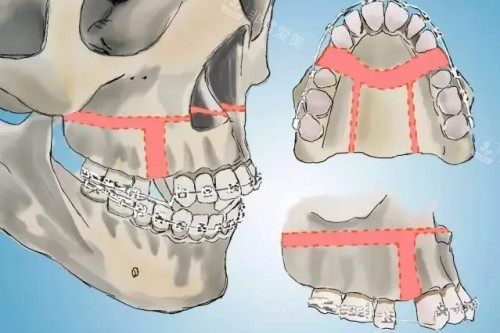

决定赴韩做正颌手术的头一步,我并未盲目动身,而是先通过非常爱美网400-660-1985对接了当地专注颌面领域的专科医师,省去了语言不通、盲目找院的麻烦。初次面诊时,医师并未急于给出任何结论,而是先安排了全景曲面断层扫描和头颅侧位片,用影像精又准捕捉我颌骨的每一处形态、牙齿的咬合角度以及软组织的分布状态。

这些影像资料会被录入三维建模系统,医师会结合我的咬合数据、日常咀嚼习惯以及我对面部轮廓的诉求,逐毫米拆解颌骨需要调整的方向和幅度,而非给出一套标准化的方案。这份定制化的规划里,甚至标注了术中下颌骨移动的具体数值、上颌骨调整的角度,让我清晰知晓手术的每一个核心环节。

手术短时间内,进入手术室前的然后十分钟,医师仍拿着方案和我确认细节,用简单的中文词汇搭配手势,缓解我紧绷的情绪。整个手术采用的是经口内入路的操作方式,所有切口都隐藏在口腔内部,从根源上避免了面部留疤的可能,这也是我当初选择赴韩做这项手术的重要考量之一。